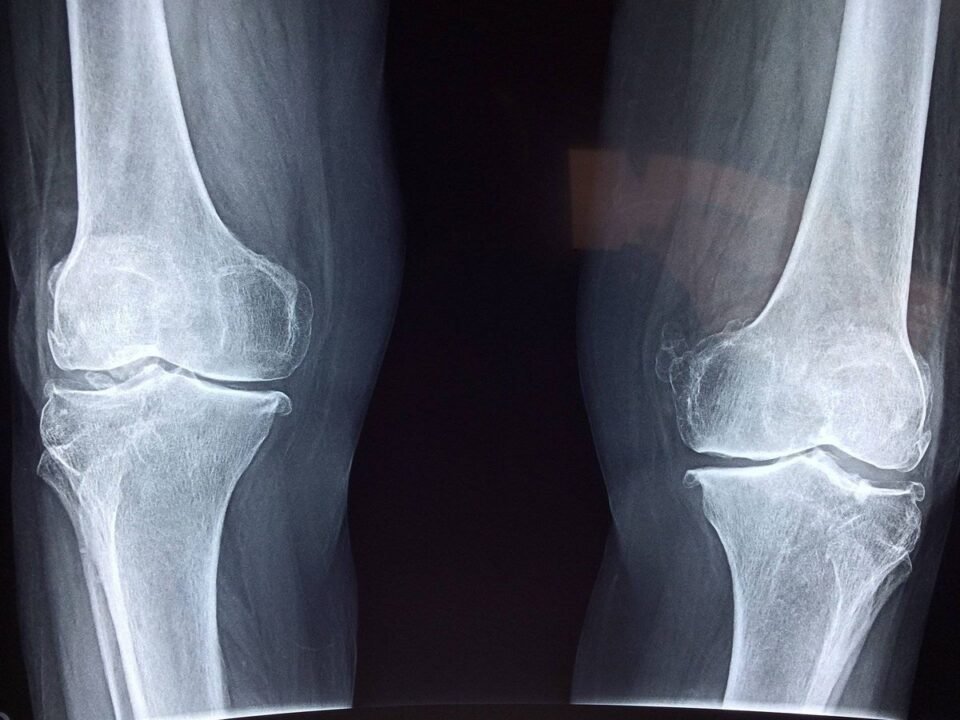

Este proyecto, que requirió de diez años de trabajo científico riguroso, ha demostrado su potencial en pruebas in vitro y en modelos animales. Los resultados son contundentes: no solo se logró la regeneración del hueso, sino que el tejido reparado exhibió una calidad superior. Las pruebas mecánicas mostraron que los huesos tratados con esta terapia podían soportar mayor peso, con una combinación ideal de rigidez y flexibilidad.